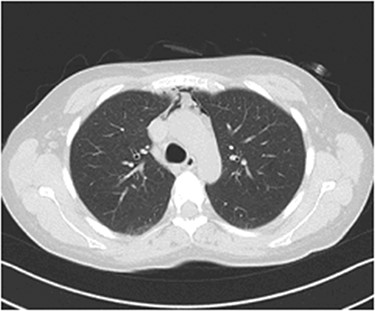

Our patient was put under oxygen therapy (Venturi 50%). As a precaution, antibiotic therapy was administered (teicoplanin/metronidazole), in order to prevent mediastinitis. During the second postoperative day, the clinical presentation of our patient was improved. The following day, the Venturi mask was replaced with a nasal cannula. In the fourth postoperative day, a computed tomography (CT) of the thorax was performed (Fig. 2), which showed a reduction of the amount of the air in the mediastinum, in concordance with the improvement of the clinical presentation of the patient. During the last day of hospitalization, the patient had no respiratory pathology symptoms, her clinical presentation was even more improved and she was discharged from the hospital on postoperative day 5.

Thorax CT during the fourth postoperative day: a significant reduction of the mediastinal gas collection is observed.